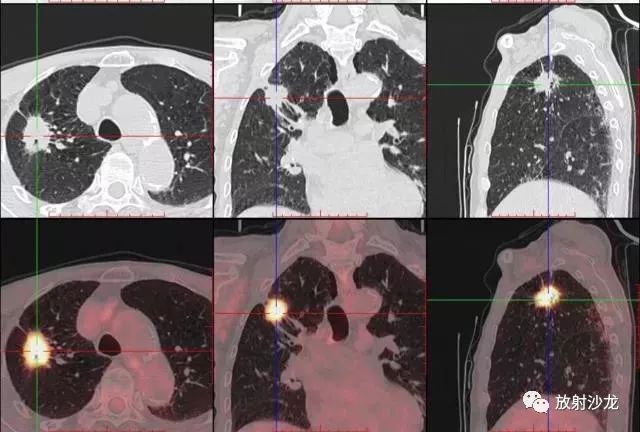

PET-CT等于PET+CT,包含PET(功能分子影像)與CT(解剖影像)的最優(yōu)化組合;即同時具有PET和CT的功能,但它絕不是二者功能的簡單疊加,因為PET與CT優(yōu)勢互補,“1+1>2”。PET-CT除了具備PET和CT各自的功能外,其獨有的融合圖像,將PET圖像與CT圖像融合, 可以同時反映病灶的代謝,可以早期診斷疾病的同時,明顯提高診斷的準(zhǔn)確性。